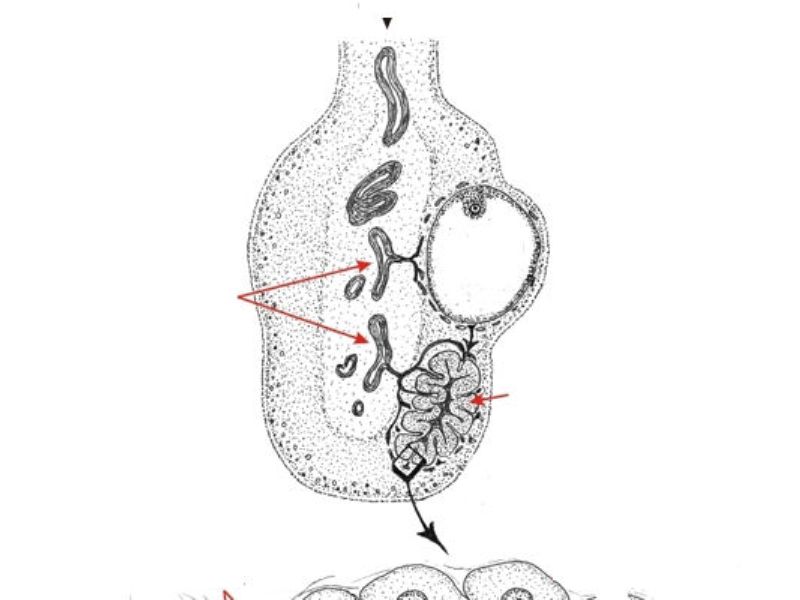

Corpus luteum

Slide 91

Corpus luteum

- Two major cell types

- Granulosa lutein cells

- modified granulosa cells

- Theca lutein cells

- modified theca interna cells

- Many capillaries

Granulosa lutein cells

- Modified granulosa cells

- Large - 30µm

- Pale cells

Theca lutein cells

- Modified theca interna cells

- Smaller - 15µm

- Dark stained